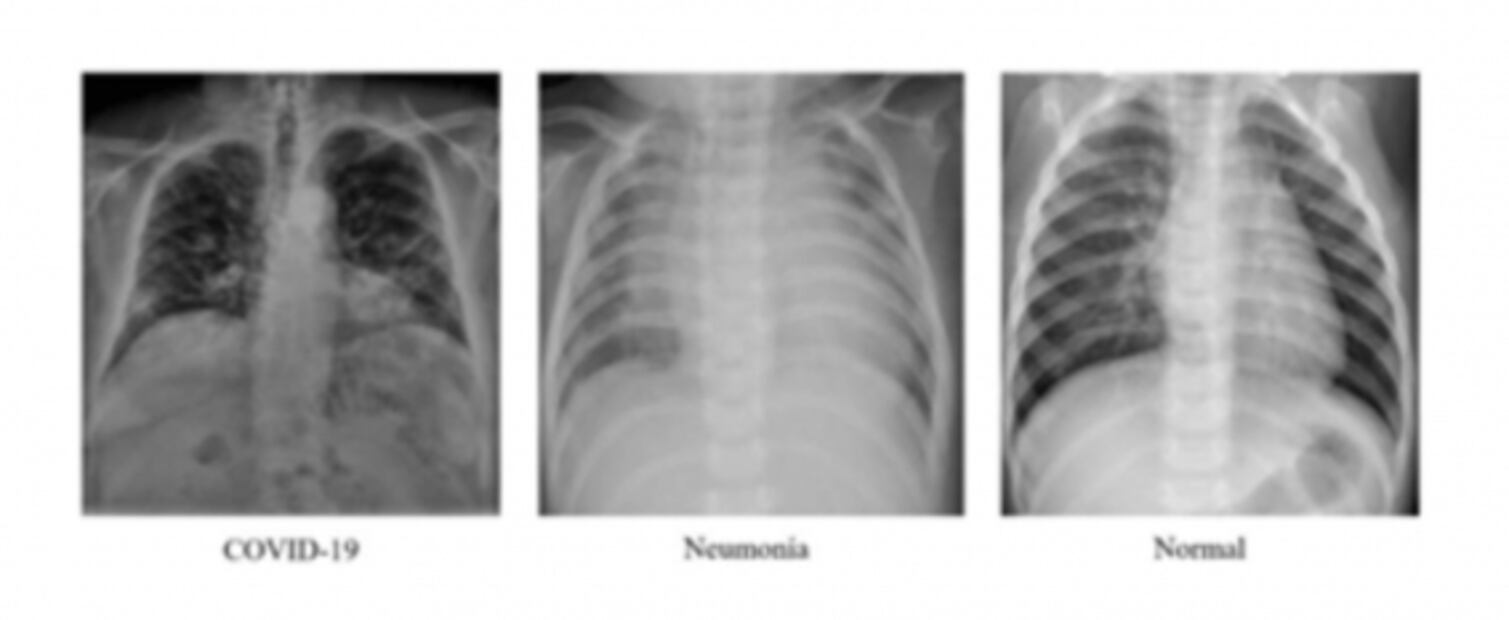

Desde marzo del año pasado, los estudiantes se dieron a la tarea de recopilar una base de datos de mil 800 imágenes de pacientes diagnosticados con Covid-19 , con neumonía y también de personas sanas.

Con la ayuda de esta base datos inicial los universitarios indicaron a su sistema que estudiara las imágenes, para que pudiera diferenciar las características de cada patología .